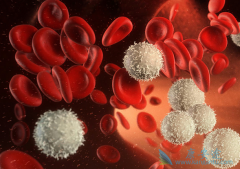

相信许多人或多或少都听说过慢性粒白血病,白血病是一种从小孩儿童到成年人都会患上的一种癌症恶性肿瘤,对于我们国内的白血病患者来说,早期症状还是比较明显的。如果能在早期发现我们慢性粒白血病患者的病情,那么我们的治疗手段也会相应发生改变,治 ...

血癌 又称白血病,是一种发病率比较高的疾病,近年来,血癌有发病人群也来越来越年轻的趋势,很多儿童也患有血癌。血癌发病前期通常会有一些症状,但是由于血癌的很多症状与感冒相似,所以并没有引起重视,从而造成更严重的疾病。下面就来看一下血癌的 ...